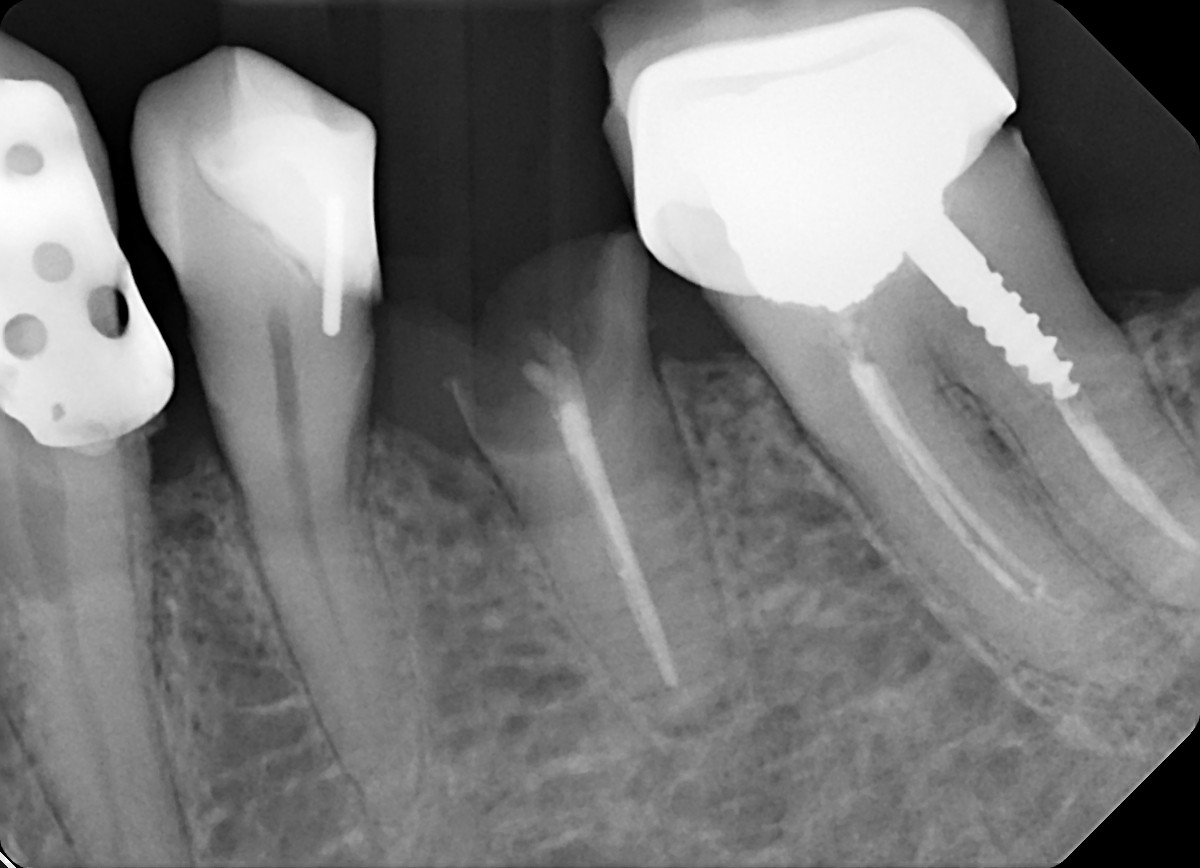

19 / 35

19. On which surface a recurrent caries can be detected?

This is the PA X ray of the question # 18, based on this X ray recurrent X ray for distal tooth # 3.7 can also be selected

20 / 35